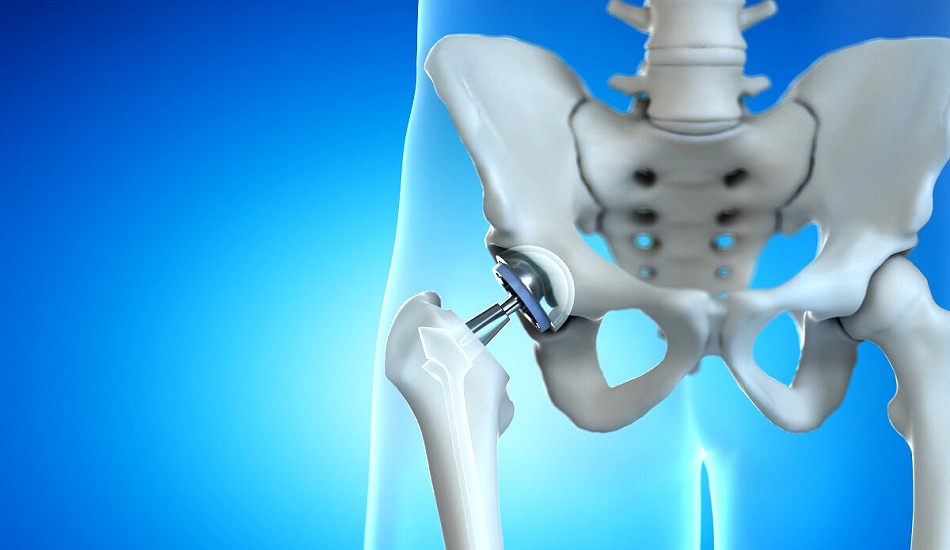

A painful or failing hip replacement occurs when an artificial hip joint no longer functions as intended, leading to discomfort, instability, or loss of mobility. This situation can arise for several reasons, such as implant wear and tear, loosening, infection, or fractures around the implant. While hip replacements are designed to last for many years, complications may develop over time, requiring medical intervention or revision surgery to restore comfort and mobility.

• Loosening of Components: Loosening occurs when the implant separates from the bone or the surrounding cement. This can result from natural bone loss, the body’s reaction to the implant, or improper placement of the prosthetic. Loose components can cause pain, instability, and reduced range of motion.

• Implant Malposition: Accurate positioning of the implant is crucial to the success of a hip replacement. If the components are misaligned or incorrectly positioned, it can lead to abnormal wear, joint instability, and an increased risk of dislocation.

• Dislocation: If the ball of the prosthetic hip pops out of the socket, it results in a dislocated hip. This is more likely to occur if the implant components are not aligned correctly or if the surrounding soft tissues are too weak to stabilise the joint.